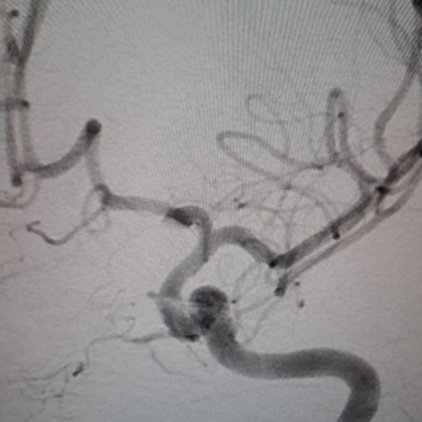

We provide devices and treatment of complex brain aneurysms and vascular malformations free of cost. These are some of the complex brain aneurysm we have recently treated in Pakistan. Devices and catheters used for all procedures were provided by Pakistan Stroke Initiative, and in some cases charges for hospitalization as well.

Although we typically don’t take photos of our patients and their families, many of those we have treated have made special requests for it. Visiting physicians from abroad have consistently been impressed by the gratitude and appreciation shown by our patients and their families for the care they receive.

All of these photos have been shared with the permission of the patients and their families.